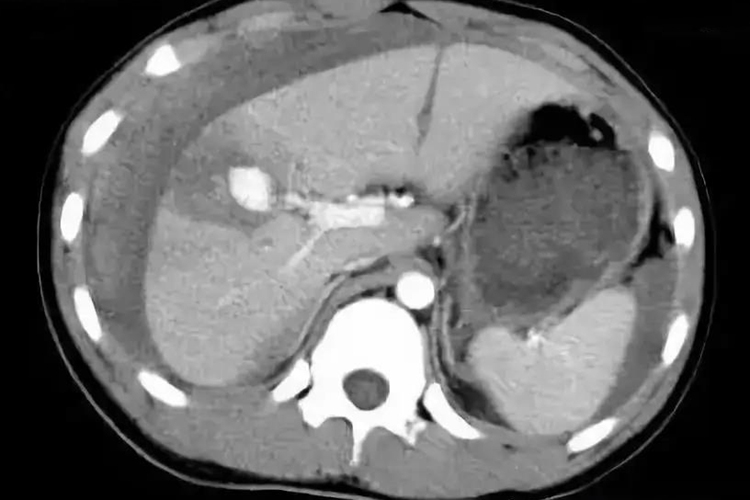

肝破裂多由坠落、机械性损伤导致,CT影像表现为肝实质破裂、肝血肿等,根据破裂的范围以及血肿的情况可分为Ⅰ-Ⅵ级。

肝破裂的CT影像主要表现为肝实质损伤、破裂,以及肝出血导致血肿,根据损伤范围不同可分为Ⅰ-Ⅵ级,级别越低,损伤程度越低,例如Ⅰ级血肿小于1%的肝表面积,肝被膜撕裂,肝实质破裂深度小于1cm,而V级或Ⅵ级时肝实质破裂超过75%肝叶,肝脏从肝蒂上撕脱。